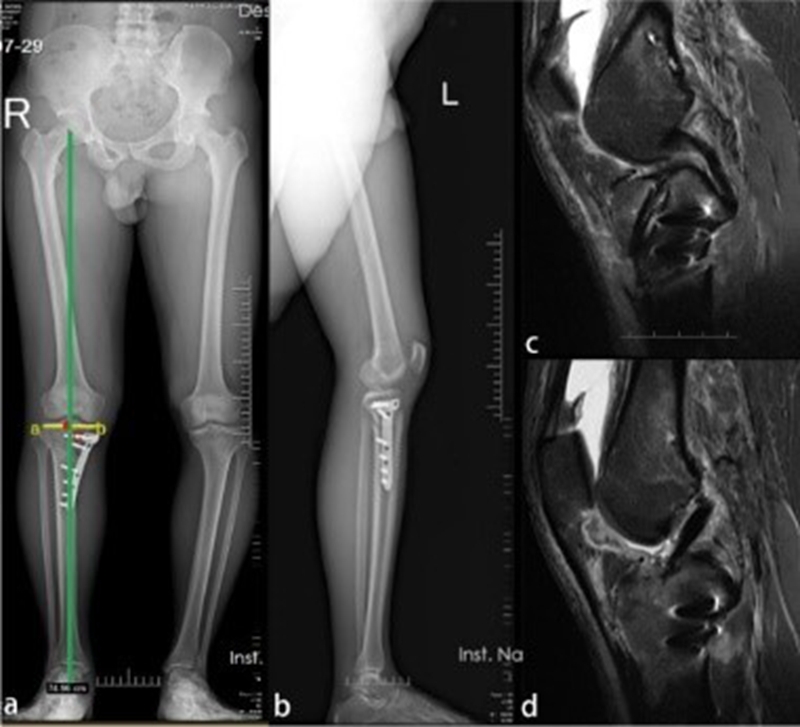

Deng等人报道一例ACLR联合OWHTO治疗膝内翻合并ACL撕裂的病例。一名27岁男性因运动损伤入院,诊断为与内翻畸形和胫骨后倾过大相关的ACL撕裂。之后,该患者接受了ACLR联合OWHTO以纠正内翻畸形和过大的胫骨后倾角[7]。

图5